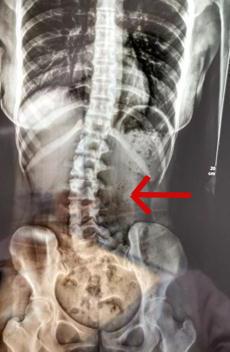

“正值 18 岁的女生小邹(化名),经常因腰痛、脖子酸等症状,并且情况逐渐严重。于是来到医院就诊,医生检查发现脊柱严重侧弯,经过x光检查,发现她的腰椎向右侧弯、旋转,并以腰 2 椎体为中心向右侧弯,脊柱向右发生明显侧弯。”

小邹的脊柱明显侧弯。广医三院图医生经过问诊后发现竟是因为她的睡眠姿势不对。

小邹长时间侧躺睡而且是侧同一边,并且下腿摆姿不正确。“患者是因为其睡姿不当,原有正常的脊柱体态在日积月累的错误睡姿中逐渐失衡,骨盆与脊柱位置变化,脊柱就发生了侧弯。”